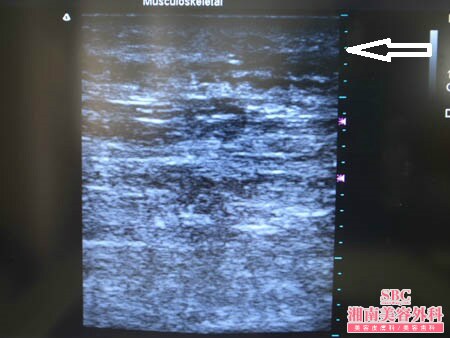

No.128950【脂肪吸引】YouTube手術関連動画掲載数・世界第一位! あの有名な根こそぎ竹田先生の劇的ビフォーアフター!〜4回目の脂肪吸引!他院の取り残しを3Dタッチビュー併用ライポマティック脂肪吸引で根こそぐ!右太もも後面3Dタッチビューその1〜